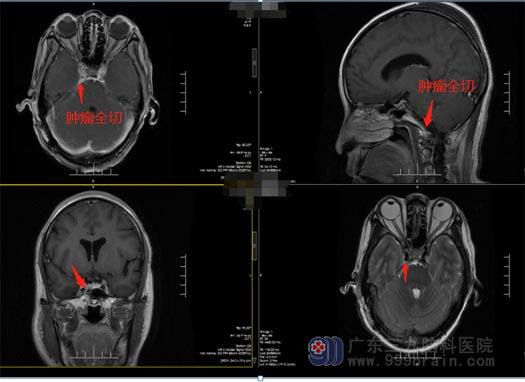

在神经外五科治疗团队的共同努力下,综合考虑手术难度、病人情况等,决定全麻下实施右侧斜坡脑膜瘤切除术+硬脑膜修补+颅骨成形术。手术顺利,中后组颅神经、动静脉保留完整,脑干保护良好,肿瘤全切,术后未发现脑出血和脑梗塞情况。

▲术后